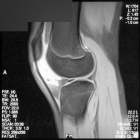

A.S. - 16 year old female c/o left anterior knee pain and swelling for one year. Worse with cheerleading, activities. Does not recall any specific trauma prior to its onset.

Zoom image: Radiological image Radiological image.